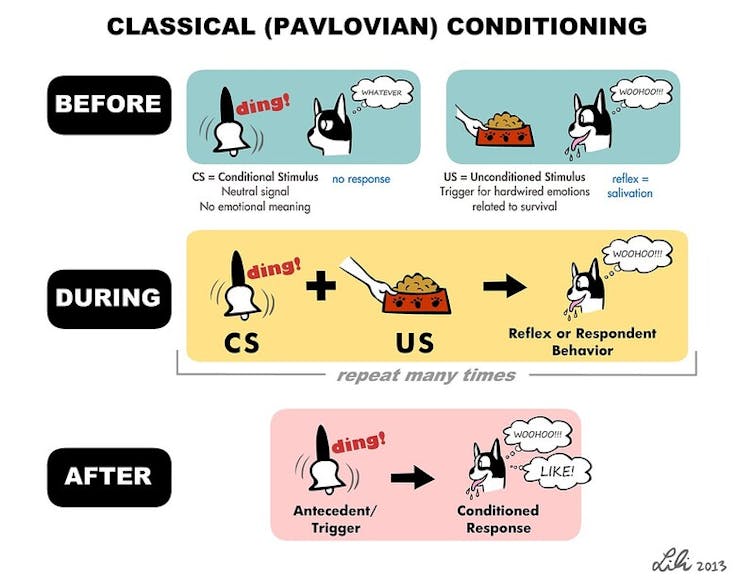

To induce a new memory in the fish, we used a type of learning process called classical conditioning. This involves exposing an animal to two different types of stimuli simultaneously: a neutral one that doesn’t provoke a reaction and an unpleasant one that the animal tries to avoid. When these two stimuli are paired together enough times, the animal responds to the neutral stimulus as if it were the unpleasant stimulus, indicating that it has made an associative memory tying these stimuli together.

As an unpleasant stimulus, we gently heated the fish’s head with an infrared laser. When the fish flicked its tail, we took that as an indication that it wanted to escape. When the fish is then exposed to a neutral stimulus, a light turning on, tail flicking meant that it’s recalling what happened when it previously encountered the unpleasant stimulus.

Associative memories tend to be much stronger than other types of memories, such as conscious memories about what you had for lunch yesterday. Associative memories induced by classical conditioning, moreover, are thought to be analogous to traumatic memories that cause PTSD. Otherwise harmless stimuli similar to what someone experienced at the time of the trauma can trigger recall of painful memories. For instance, a bright light or a loud noise could bring back memories of combat. Our study reveals the role that synaptic connections may play in memory, and could explain why associative memories can last longer and be remembered more vividly than other types of memories.

Currently the most common treatment for PTSD, exposure therapy, involves repeatedly exposing the patient to a harmless but triggering stimulus in order to suppress recall of the traumatic event. In theory, this indirectly remodels the synapses of the brain to make the memory less painful. Although there has been some success with exposure therapy, patients are prone to relapse. This suggests that the underlying memory causing the traumatic response has not been eliminated.